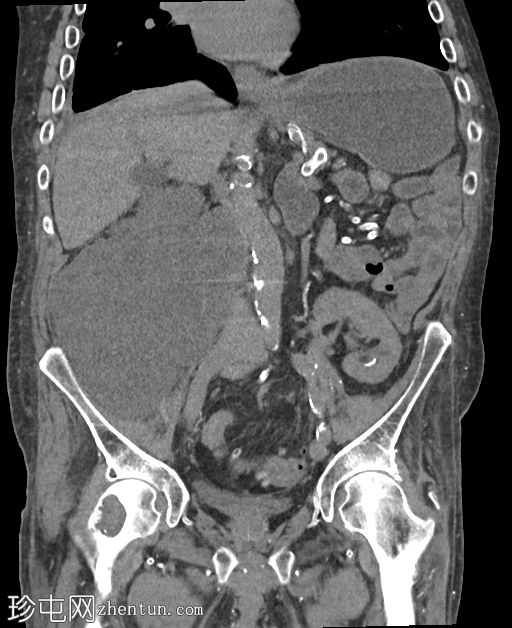

右髂窝移植肾不规则且受压,肾周可见巨大分叶状肿块,T2呈高信号,并进行性不均匀强化。这是黏液样变性的典型表现。

为确诊肾周脂肪黏液样假瘤,进行了活检。该假瘤是慢性肾脏炎症背景下的良性反应性病变,并非真正的肿瘤。最终行移植肾切除术,切除标本大小为26 x 18 x 12 cm,再次证实了诊断。

该过程反映了肾周脂肪组织的黏液样变性和纤维增生,本质上是指肾周脂肪中含有水肿的、富含黏蛋白的/黏液样结缔组织,具有典型的CT和MRI表现(T2高信号,轻度/中度强化)。鉴别诊断可能包括脂肪肉瘤以及与慢性炎症/黄色肉芽肿感染相关的并发症。